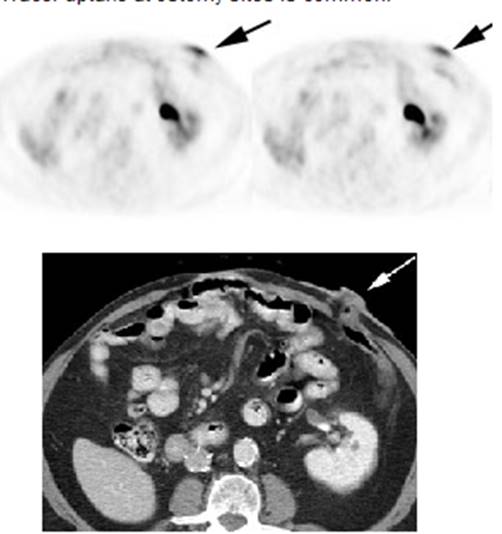

Figure 20 - Ostomy sites: Tracer uptake at ostomy

sites is common